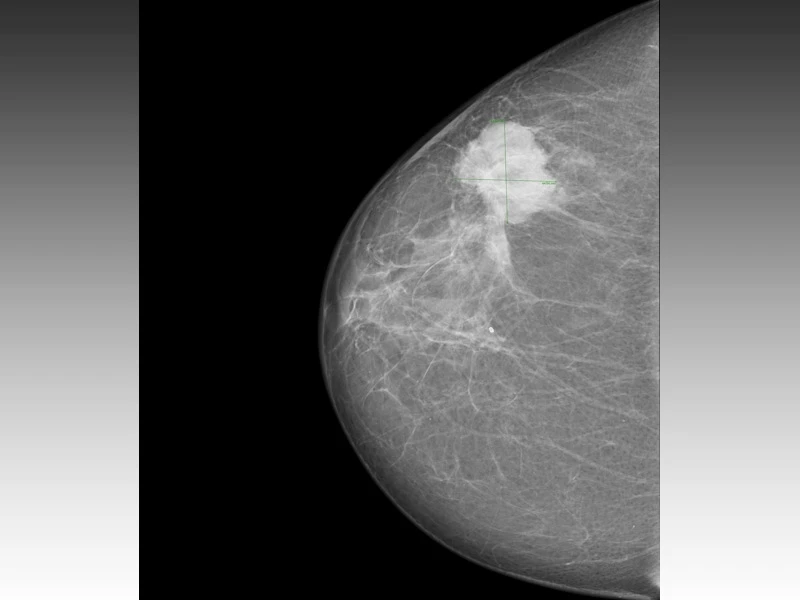

Você está precisando de um mastologista para homens preço Vila Madalena? A Clínica Bem Estar pode ajudá-lo. Apesar de raras, algumas doenças mamárias podem estar presentes nos homens. Como exemplo, a ginecomastia, que é responsável por 85% das massas palpáveis na mama masculina. Temos, ainda, o câncer de mama que incide em 0,8-1% dos homens e, normalmente, está associado a alguns fatores de risco.